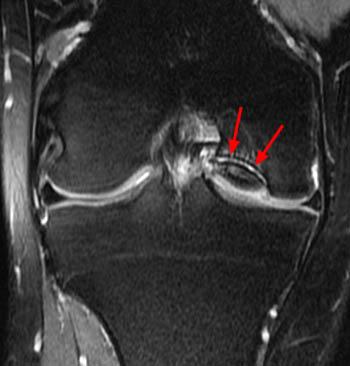

Request an appointment using our secure online form. Chondrolysis of the Glenohumeral Joint - Radsource

Chondrolysis of the Glenohumeral Joint - Radsource from radsource.us